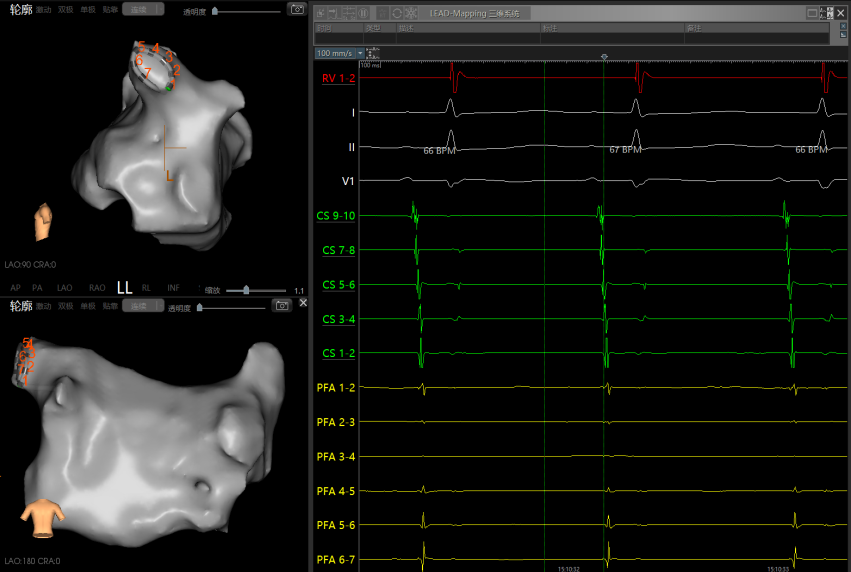

术中左侧和右侧肺静脉电位

左侧肺静脉消融触发房扑,先从左侧肺静脉开始消融,消融时触发短阵房扑,形态不断变化。优先隔离肺静脉,做完PVI后再观察房扑是否存在。

PVI后房扑:肺静脉隔离后,房扑仍在发作且持续稳定,CS90早,周长220-230ms,遂进行激动标测。